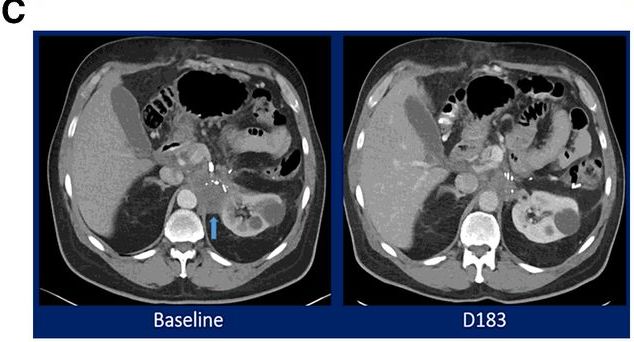

49岁HPV感染阳性的女性转移性宫颈癌患者,在接受顺铂/紫杉醇后加贝伐单抗治疗,随后病情进展,出现两个病理性扩大的纵隔淋巴结(图左侧箭头)。入组M7824的临床试验后,在用药7.5个月后奇迹出现,CT扫描显示达到完全缓解,在13个月的再次扫描仍未发现病灶,证明反应是持久的(图的右侧)。CEA持续下降!

图B证实患者的CEA持续下降